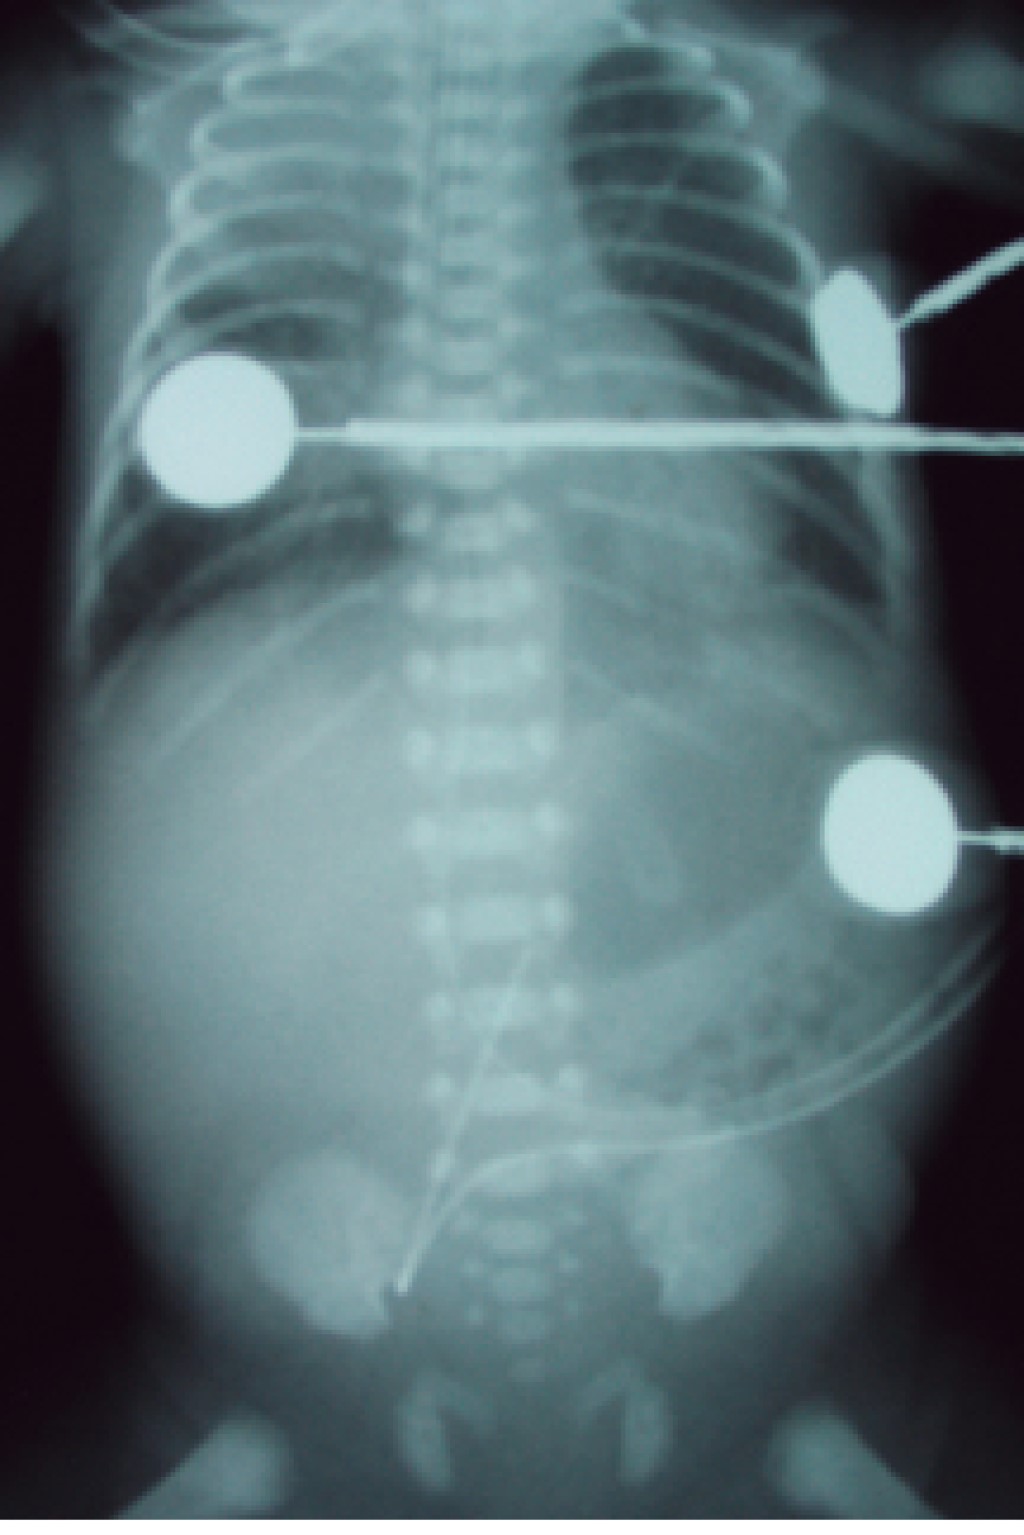

El trayecto que normalmente debe recorrer el catéter venoso umbilical para que quede en la posición correcta es el siguiente: se introduce por la vena umbilical, llegando al primer receso venoso umbilical, lugar al que llegan las venas portales derecha e izquierda y donde inicia el conducto venoso de Arancio con una longitud de 1 a 2 cm y posteriormente llega al segundo receso umbilical, lugar al que llegan las venas hepáticas derecha e izquierda, y en seguida pasa a la vena cava inferior para terminar en la entrada de la aurícula derecha (Figuras 2 y 4). Generalmente, el catéter sigue el trayecto descrito; sin embargo, sucede en ocasiones que se puede desviar a múltiples lugares según la vena por la cual se deslizó y, por lo tanto, queda en posición anómala, lo que podría provocar múltiples complicaciones, por lo que idealmente se debe solicitar una radiografía toracoabdominal al término de la colocación del catéter para corroborar su posición y, de ser necesario, realizar las correcciones convenientes antes de fijarlo y de retirar el campo estéril. Una vez retirado el campo estéril, un catéter mal posicionado que se encuentre por arriba del sitio correcto sí podrá ser retirado algunos centímetros para dejarlo en posición correcta. Cuando la punta del catéter queda por debajo del hemidiafragma derecho, ya sea en el trayecto normal o en una de las venas del sistema venoso umbilical, no podrá introducirse para dejarlo en una posición correcta, ya que el riesgo de infección es alto, pero sí podrá retirarse algunos centímetros para dejarlo en alguno de los vasos del trayecto normal (Figura 5). Recordar que cuando la punta del catéter venoso queda en cualquier sitio del trayecto normal nunca se podrán manejar soluciones hiperosmolares (> de 800 mOsm/L), ante el peligro de causar daño al endotelio vascular e incluso perforación del vaso. El catéter venoso umbilical puede tener una posición baja, la cual se sitúa de 2-4 cm por debajo de piel de pared abdominal. Esta posición baja se coloca al momento del nacimiento, cuando el recién nacido se encuentra en malas condiciones y requiere de una infusión rápida de líquidos, medicamentos o hemoderivados, no se debe introducir en estos momentos de la reanimación más centímetros, porque se puede situar el catéter en una posición incorrecta y ésta podría hacer que se dirija a la vena portal derecha, infundir los productos al hígado y causar daño importante a este órgano (Figura 6).7

• 2. Se pueden diferenciar radiológicamente por su trayecto anatómico, el catéter venoso al entrar a pared abdominal se dirige hacia dirección cefálica y se sitúa en el lado derecho de abdomen y el arterial al entrar a pared abdominal se dirige hacia dirección podálica, de tal forma que baja para entrar a la arteria iliaca interna derecha o izquierda y hace un bucle para ascender por las iliacas y llegar a la arteria aorta, situándose ligeramente por el lado izquierdo del abdomen.

• 5. El catéter arterial siempre se fija en el lado derecho del abdomen, entre el mesogastrio y flanco derecho; y el catéter venoso en el lado izquierdo, entre el mesogastrio y flanco izquierdo (Figuras 10 y 11).

• 6. En una radiografía tangencial de abdomen y tórax, los catéteres tienen una distribución muy particular, el venoso se dirige siempre hacia dirección cefálica, hacia arriba por la pared abdominal anterior para pasar a un lado del hígado y llegar al corazón derecho. El catéter arterial se dirige siempre hacia dirección podálica, hacia abajo de la pared abdominal hasta alcanzar la arteria iliaca interna derecha o izquierda y de esta forma ascender para llegar a la arteria aorta, haciendo un bucle y correr por encima de los cuerpos vertebrales lumbares y dorsales (Figuras 12 y 13).